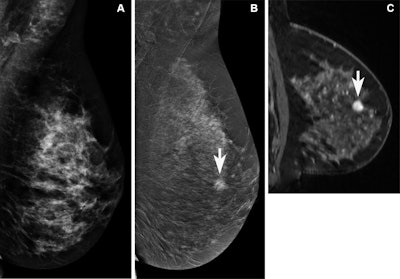

A 47-year-old female participant with a suspicious mass noted at screening tomosynthesis and subsequent diagnostic ultrasound was recruited for contrast-enhanced mammography (CEM) and MRI. (A) No abnormality was noted on the conventional 2D mammogram showing dense breast tissue. A mass (arrows) was clearly observed on (B) the recombined CEM image and (C) the MRI scan. Both images show marked background parenchymal enhancement. Biopsy confirmed a 1.1-cm grade 2 invasive ductal carcinoma (estrogen receptor- and progesterone receptor-positive, human epidermal growth factor receptor 2-negative). Image courtesy of Radiology.